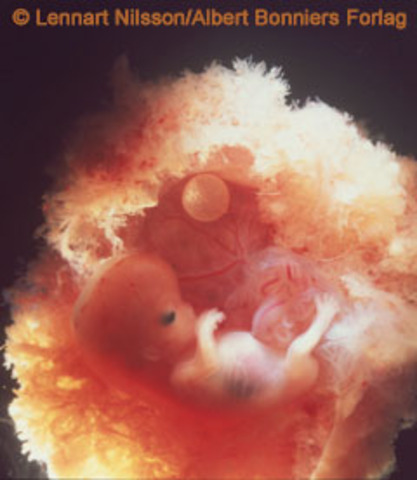

• 9 weeks

9 weeks

The embryonic "tail" is completely gone. Your baby's organs, muscles, and nerves are kicking into gear. The external sex organs are there but won't be distinguishable as male or female for another few weeks. Her eyes are fully formed, but her eyelids are fused shut and won't open until 27 weeks. She has tiny earlobes, and her mouth, nose, and nostrils are more distinct